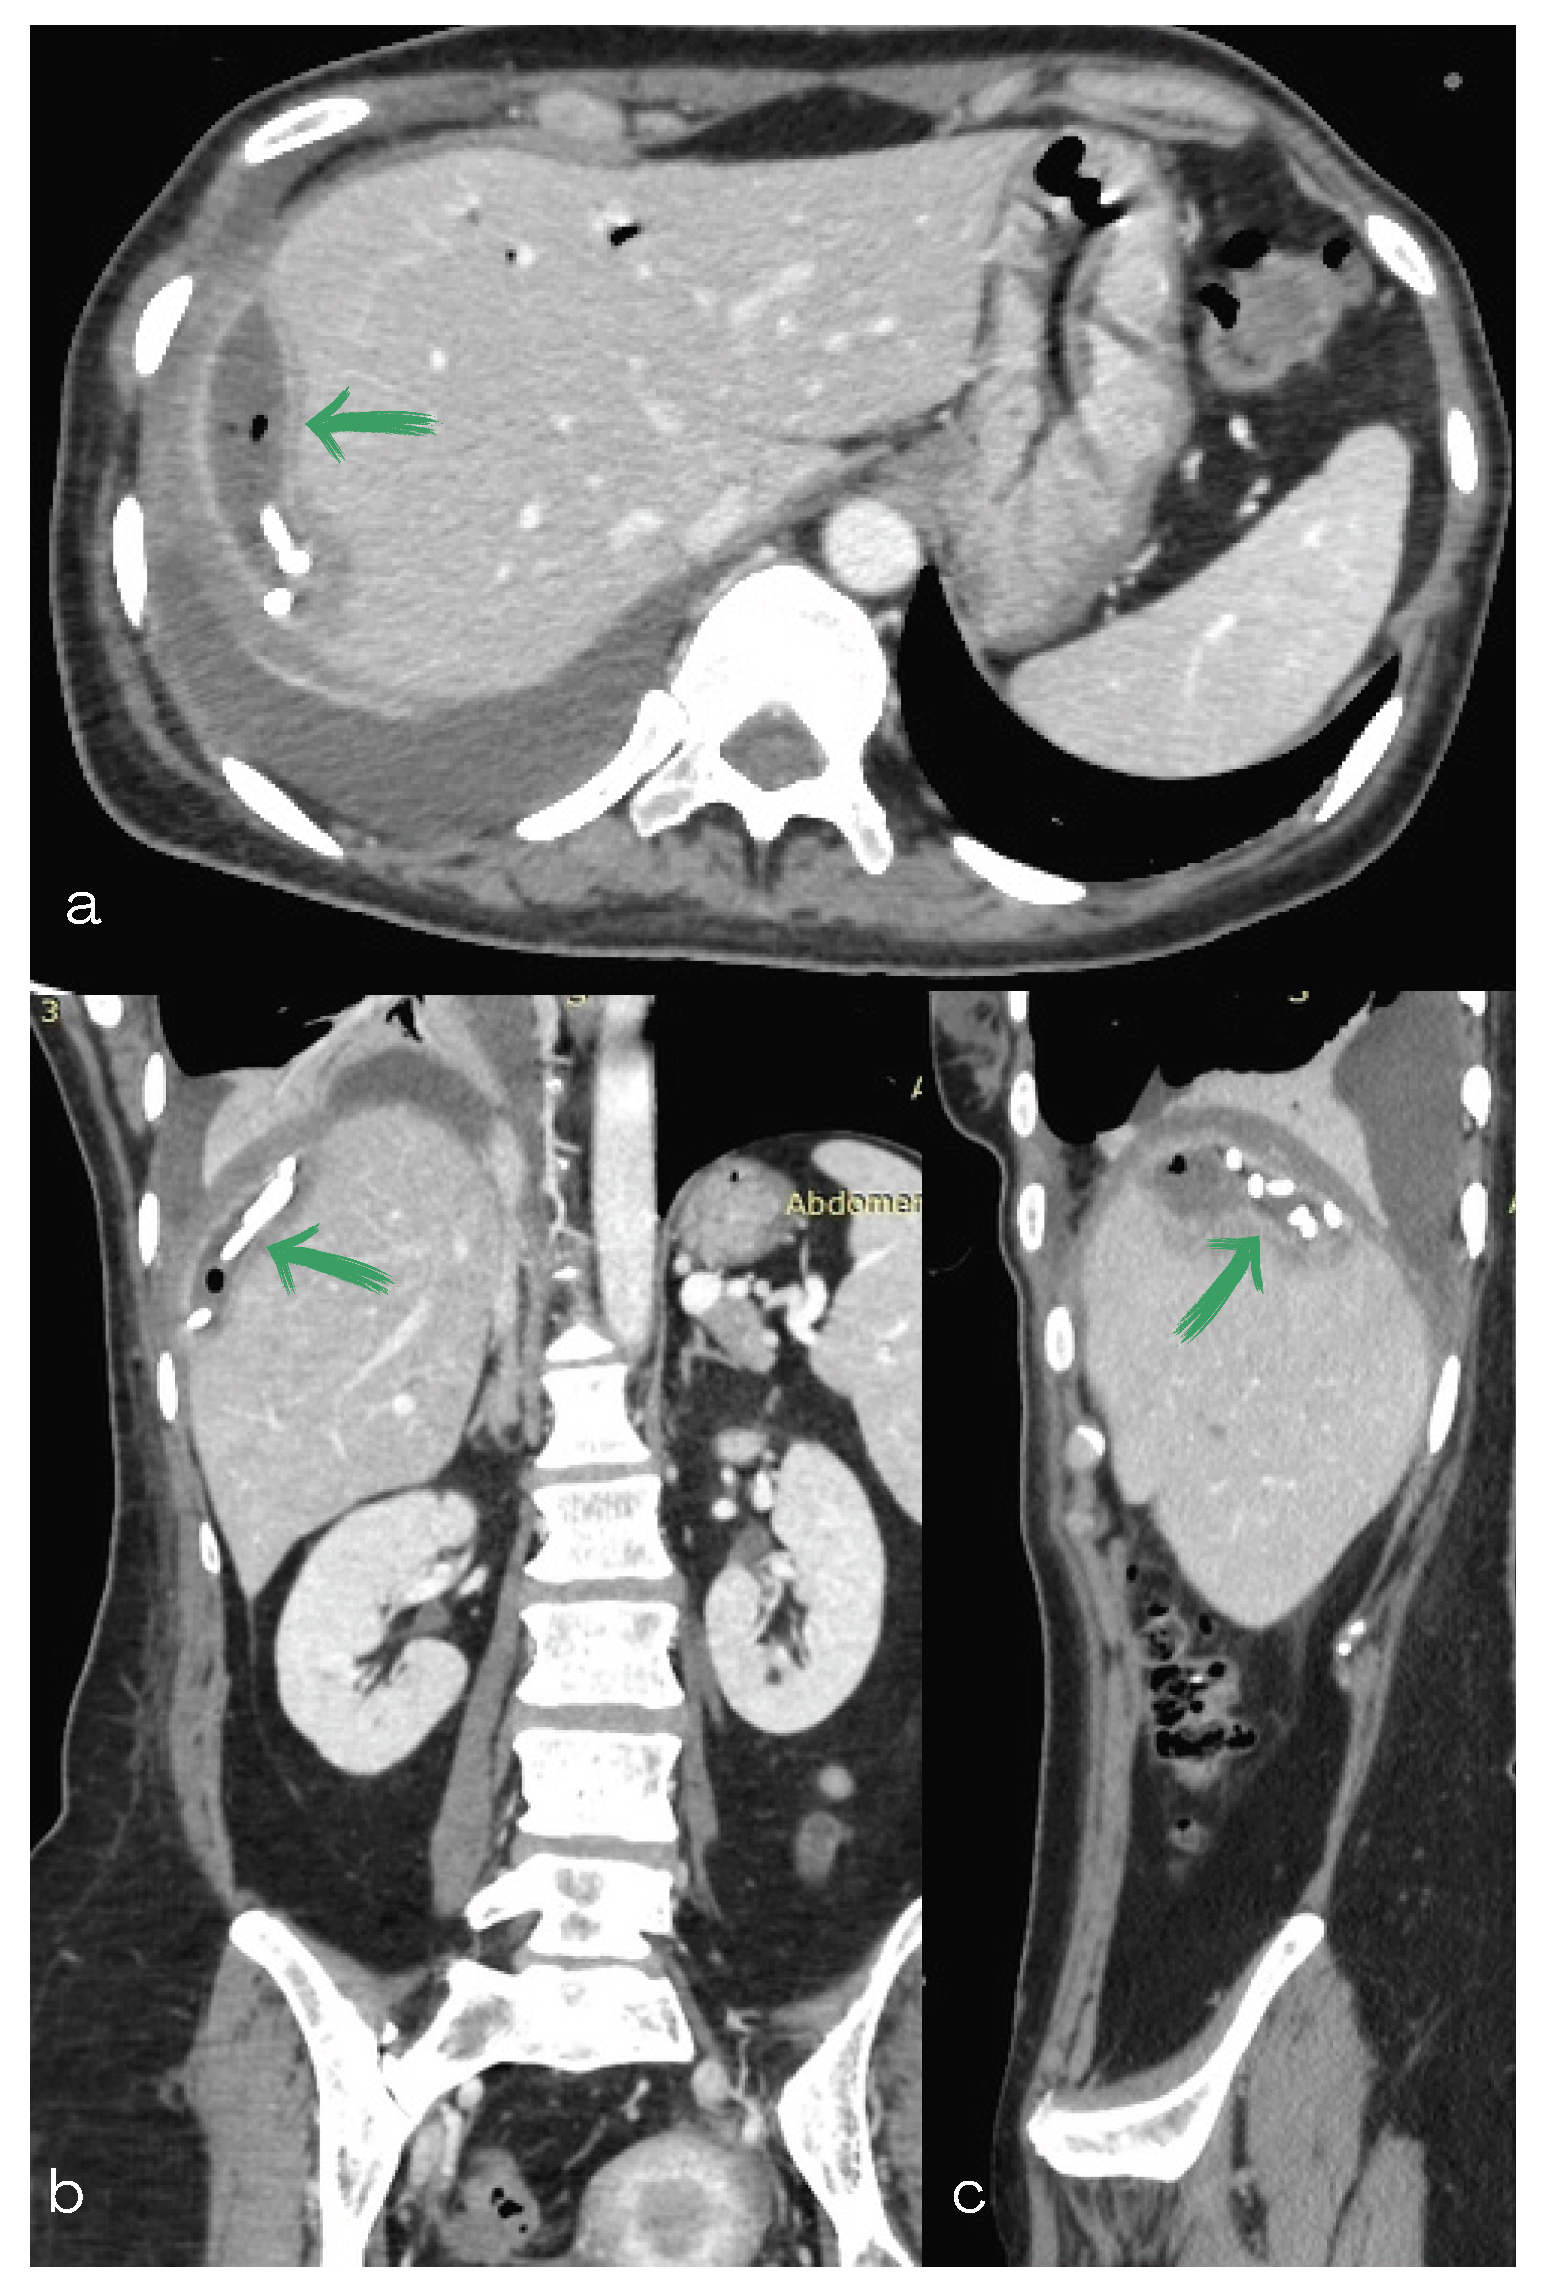

2. Case Report